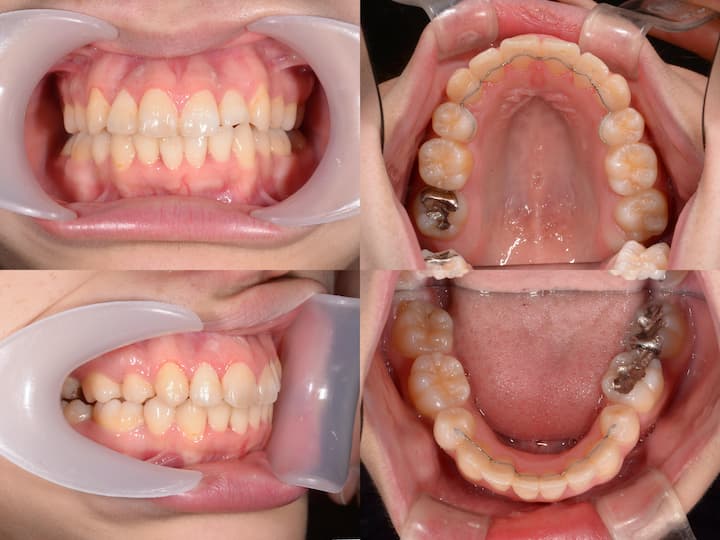

叢生と口元の突出感のハーフリンガル矯正

治療期間: 1年5ヶ月

症例概要

本症例は、叢生および口唇部の突出感を主訴とする患者様に対し、ハーフリンガル矯正装置(上顎舌側・下顎唇側)を使用して治療を行いました。

下顎骨の後方位を伴うハイアングル症例であったため、上顎大臼歯の圧下を治療計画に組み込み、下顎骨のアンチクロックワイズローテーション(反時計回り回転)を誘導することで、口唇部の突出感改善と良好な咬合関係の確立を目指しました。

初診時年齢:27歳2ヶ月

主訴:歯列不正および口唇部の突出感

初診時の口腔内所見および頭部X線規格写真分析より、以下の所見が認められました。

・上下顎前歯部の叢生

・口唇部の突出感

・AngleⅠ級臼歯関係(良好な臼歯関係)

・下顎骨の後方位(ハイアングル症例)

・下顎下縁平面角の増大

本症例の特徴は、良好なAngleⅠ級臼歯関係を有する一方で、下顎骨の後方位により口唇部の突出感が生じている点です。

このような症例では、単純な抜歯スペース閉鎖だけでなく、垂直的な咬合改善が重要となります。

・上下左右第一小臼歯の抜歯による叢生の改善

・上顎大臼歯の圧下による下顎骨のアンチクロックワイズローテーション誘導

・AngleⅠ級臼歯関係の維持

上顎大臼歯の圧下により下顎骨を反時計回りに回転させることで、オトガイ部の前方移動と下顔面高の減少を図り、口唇部の突出感を改善する計画としました。

ハーフリンガル矯正装置を採用し、上顎は舌側矯正装置(リンガルブラケット)、下顎は唇側矯正装置(ラビアルブラケット)を使用しました。

・i-station(歯科矯正用アンカースクリュー)の植立:正中口蓋縫合部に植立し、上顎大臼歯の固定源として使用

・上顎大臼歯の圧下:i-stationからの圧下力により、上顎大臼歯を垂直的に圧下

・上顎大臼歯の固定:抜歯スペース閉鎖時の近心移動を防止し、AngleⅠ級臼歯関係を維持

・フルサイズワイヤーの使用:.018×.025インチTMA(チタンモリブデン合金)ワイヤーを使用し、臼歯部のみが選択的に圧下するように設計

・パラタルバーの装着:上顎大臼歯の幅径を維持し、歯列弓形態の安定を確保

・前歯部の垂直的位置の維持:大臼歯圧下時に前歯部が挺出しないよう、ワイヤーで適切にコントロール

総治療期間:1年5ヶ月

治療結果

上顎大臼歯の圧下により下顎骨のアンチクロックワイズローテーションが誘導され、口唇部の突出感は著明に改善されました。

また、叢生も解消され、AngleⅠ級臼歯関係を維持したまま、機能的かつ審美的に優れた咬合状態を獲得することができました。

臼歯部の咬合も良好に保たれ、患者様からも高い満足度をいただいております。

本症例は、下顎骨の後方位を伴うハイアングル症例であり、口唇部の突出感が主訴の一つでした。

このような症例では、上顎大臼歯の圧下による下顎骨のアンチクロックワイズローテーションが有効な治療戦略となります。

i-stationを用いた確実な固定源の確保と、フルサイズTMAワイヤーおよびパラタルバーによる緻密な咬合管理により、臼歯部のオープンバイトを生じることなく、大臼歯の圧下を達成することができました。

その結果、AngleⅠ級臼歯関係を維持しながら、口唇部の突出感を改善し、優れた治療結果を得ることができた症例です。